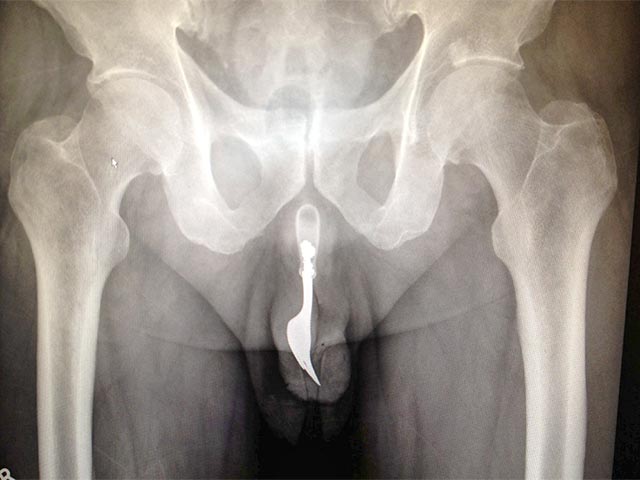

Неназванный 70-летний любитель острых ощущений попал в больницу Канберры с окровавленным пенисом, сообщает The Canberra Times. При этом вилку внутри пениса не было видно, хотя она ощущалась на ощупь и проявилась на рентгеновском снимке.

Столовый прибор вынимали из полового органа под общим наркозом, с использованием специальных щипцов и смазки. Операция прошла успешно, пожилого пациента отпустили домой.